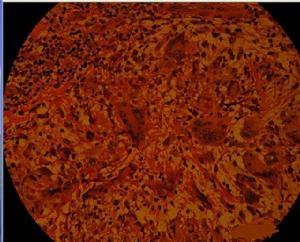

組織病理:初起為中性粒細胞浸潤,伴有壞死區,有大量的結核桿菌。2周后單核細胞和巨噬細胞浸潤占多數,後期出現上皮細胞和巨細胞,乾酪樣壞死漸減少,結核桿菌也明顯減少。